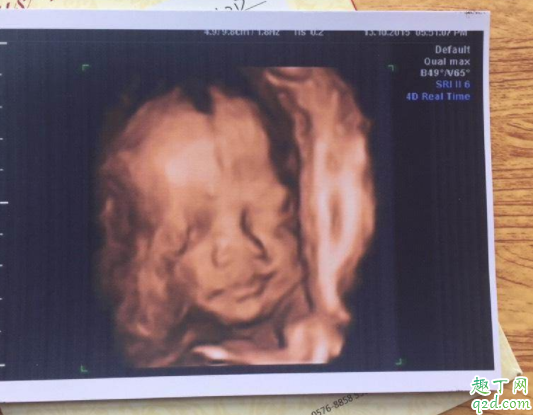

当怀孕到一定阶段的时候,医生就会建议孕妇做四维彩超,一方面可以看到孩子的四维影像,对于父母来说是激动的事情,另外一个就是可以看出胎儿有没有先天畸形 。那么孕几周做四维最好呢?要做几分钟呢?

孕几周做四维是最佳时期孕期的任何时候都可以做四维彩超,但是最佳时间为孕22周到26周之间 。

因为胎儿20周到28周左右大脑发育比较完善,22周到26周是最合适的时间,并且胎儿四肢五官心脏等内部结构已经形成,胎儿的大小以及羊水适中,在宫内的活动空间较大,胎儿整体图像也比较清晰,此时是做四维是最好的时机 。毕竟四维彩超价格较高,孕周小了也看不清 。

做四维彩超的主要是为了诊断胎儿先天畸形疾病,如唇裂、肾积水、肠道闭锁、羊水过少或过多等等 。四维彩超是大排畸的好时机,如果无特殊情况,一定要按时去做的 。